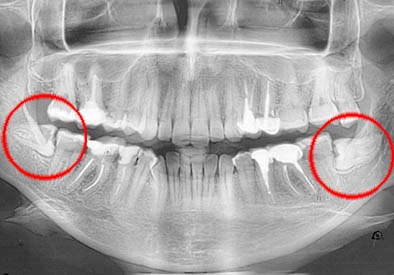

sni

Сегодня я узнал, что у меня нет и не будет зубов мудрости. Так я еще никогда не лажался! У меня было столько планов! Ущерб образу меня с зубами неисчислим…

Не, до них не дошел — оказалось, что они с моей страховкой не работают. Завел себе зубного в деревне, недалеко от дома )

А у меня справа есть и сверху и снизу, а слева нет :)))

А бывает с ними еще и не так везет :)

у меня один такой слева, походу. операцию надо будет делать (

так что тут такое дело своеобразное )

Ну это я преувеличиваю, конечно, но общий план был быть нормальным, как все нормальные люди, у которых растут эти зубы проблемные. И решать проблемы ) Просто такая вера и надежда по умолчанию, что я как все, и меня будут уважать за зубы мудрости. И мы сможем на них друг другу жаловаться.

Мне эти зубы подкинули такую мудрость: бывает такая зубная боль, от которой можно кричать в голос и прыгать, и которая ломает к чертям все твои убеждения о том, что пить таблетки — зло и занятие ненужное. А потом также догнало другой мудростью — что бывает таблетки не помогают. И что врачи могут быть заняты в течение аж 20 минут, несмотря на то, что говорит пациент с большими глазами в коридоре.

Но я почему к врачу-то пошел — что-то там болит и даже опухло! Может быть, вера прописана: «зубы мудрости пора бы и заиметь, в 25-то лет!», теперь пытаюсь имитировать даже симптомы, о которых не знал. Теперь к врачу только через неделю… Но рентген добавил ясности, так что может быть за неделю всё пройдет )

У моего мужа их тоже нет и не будет, но врач сказал, что это показатель эволюции. у последующих поколений зубов мудрости не будет. что-то типа такого

а у меня они все есть — правда рано пошли — вся челюсть болит бывает(((